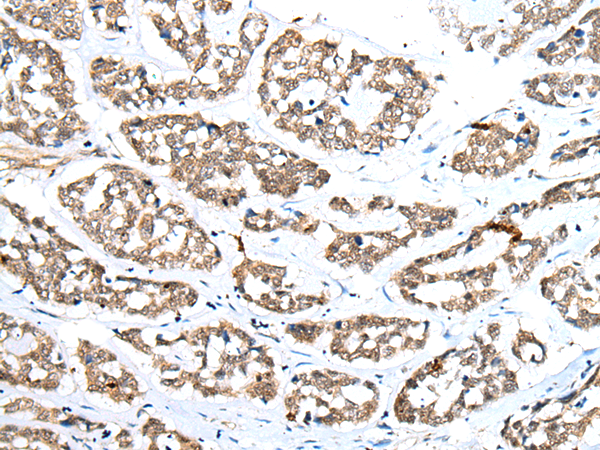

IHC positive control: |

Human esophagus cancer |

IHC Recommend dilution: |

20-100 |